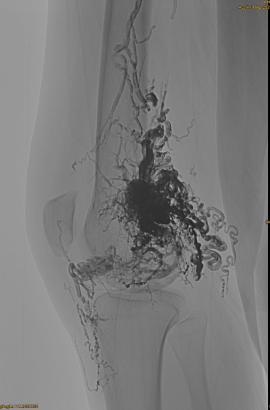

Endelig resultat:

Næppe nogen venøs udstrømning:

Sen fase, en anden EMBO nødvendig, men meget bedre: